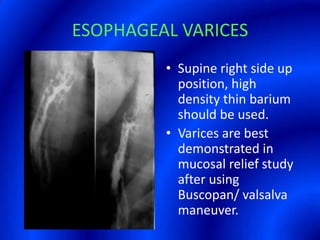

This document provides information about a barium swallow procedure. It begins with an introduction and overview of the embryology and anatomy of the pharynx and esophagus. It then describes the procedure itself, including preparation, technique, views obtained, and indications. Specific conditions that may be examined include pharyngeal and esophageal webs, foreign body impaction, scleroderma, dysphagia, mediastinal masses, and carcinoma. Diagrams are provided to illustrate normal anatomy and various pathological findings.